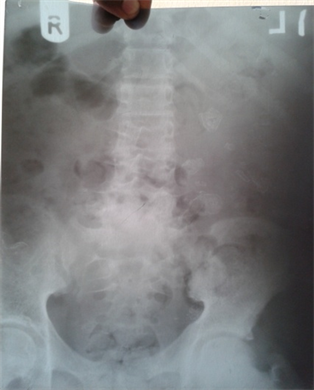

- X-Ray of the lumbosacral spine showed degeneration and collapse of the vertebrae and loss of joint spaces, involving L5, S1 and upper sacral spine, Spondylolisthesis of S1 and L5 was evident. (Figure 6 & Figure 7)

Figure 6. Degeneration collapse of vertebrae and loss of joint spaces L5, S1 Reproduced with permission.

Based on the history, positive mantoux test, Vertebral X-RAY and CXR results, a diagnosis of extra pulmonary TB (Scrofuloderma and Potts disease of the spine) was entertained. The viral warts were believed to be secondary to immunosuppression from TB. Decision was to commence full anti-Koch’s therapy immediately using Isoniazid (INH), Rifampicin, Pyrazinamide, Ethambutol according to NTBLCP guideline.